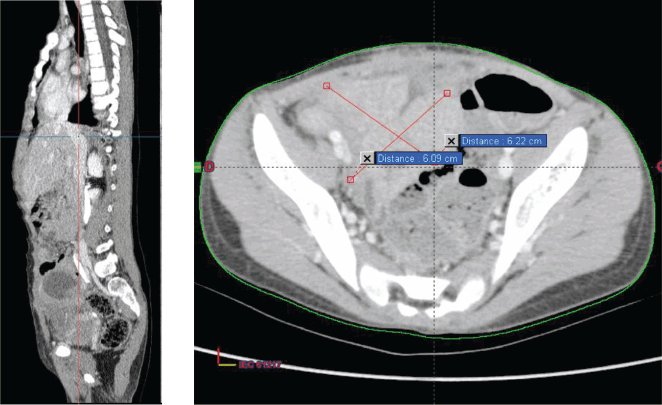

The decision made during the multidisciplinary team meeting was to proceed with the RMS 2005 protocol. Chemotherapy based on the IVA regimen was initiated 15 days after her admission. The patient received four cycles with good clinical tolerance, showing no mucositis, proctitis, diarrhoea, or signs of infection. Clinical examination revealed a reduction in tumour size from 10 to 7 cm, prompting the performance of a second thoraco-abdominopelvic CT scan (Figure 2) that shows a significant regression of the abdominopelvic tumour process, as well as pulmonary and nodal metastases, estimated to be over 70%.

Figure 2. Chest–abdomen–pelvis postchemo and preoperative CT scan showed regression of the abdominal–pelvic tumour process estimated at 70%.